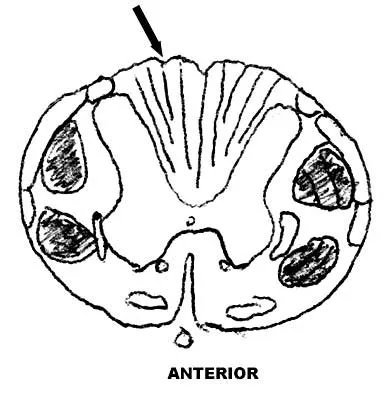

Question 100

A 16-year-old girl has a painful foot mass. A radiograph, MRI scan, and biopsy specimens are shown in Figures 35a through 35d. What is the most likely diagnosis?

Explanation